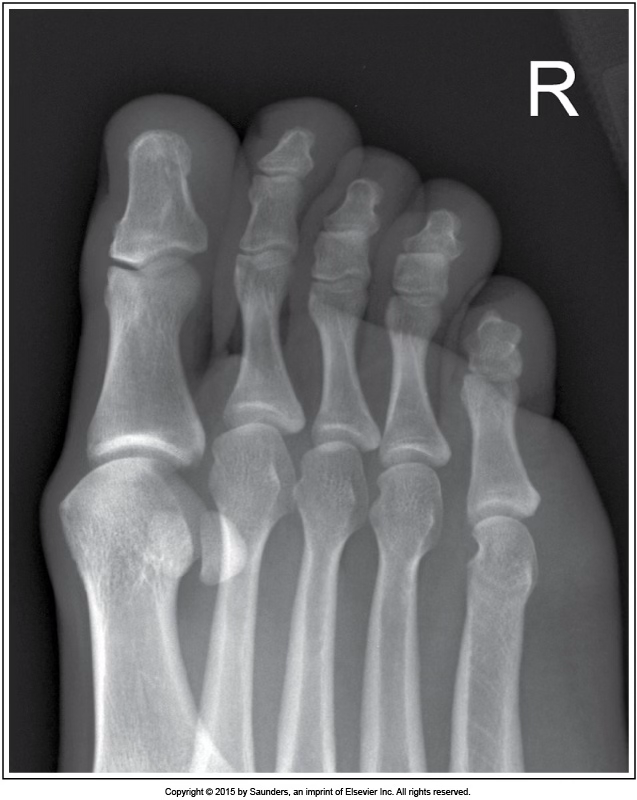

AP axial toe

accurate positioning